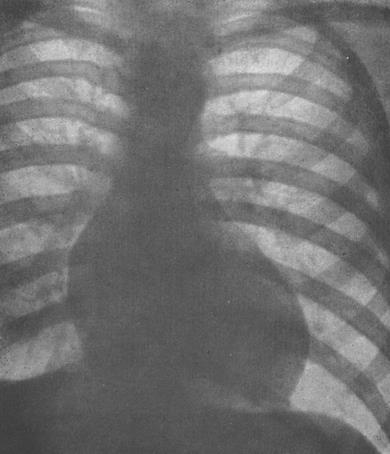

Рис. Рентгенограма грудної клітини при незначно

вираженому аортальному стенозі.